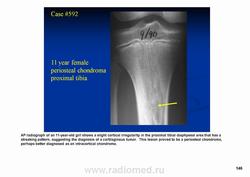

Периостальная хондрома (син.: юкстакортикальная хондрома, паростальная хондрома редкая доброкачественная опухоль, состоящая из зрелой хрящевой ткани и расположенная над надкостницей. Обычно она разрушает наружную часть коркового слоя, но не прорастает в костно-мозговой канал. Мужчины болеют в два раза чаще женщин. Типичная локализация - проксимальный конец плечевой и бедренной кости дистальный конец бедренной кости, а также фаланги. В редких случаях одновременно поражается несколько костей. Периостальная хондрома обнаруживается большей частью в метафизарной части, лишь у 30 % больных поражаются диафизы. Опухоль достигает в среднем 2-3 см в диаметре. Она окружена зоной остеосклероза и сопровождается периостальным остеогенезом, так что на границе опухоли с костью образуется грушевидное углубление с четкими контурами. Под микроскопом периостальная хондрома имеет тонкие контуры, она как бы погружена в корковый слой и покрыта надкостницей, как тонкой скорлупой. На разрезе ее ткань синюшно-серая или белая, хрящевые элементы обладают дольчатым строением. Участки обызвествления имеют вид желтовато-белых вкраплений. Эта опухоль состоит из гиалинового хряща, дольки которого разделены фиброзными прослойками или костными балками, местами обызвествленными. Кое-где отмечается проникновение опухолевых клеток в костномозговой канал, на большем же протяжении внутренний контур образован компактной костью.

Дифференциальная диагностика представляет известные трудности в тех случаях, когда периостальная хондрома имеет сходство с юкстакортикальной хондросаркомой.